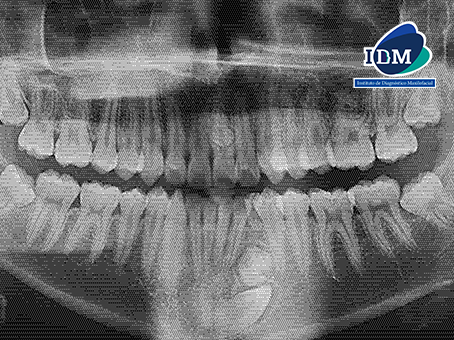

Radiografia Panorámica

En la radiografía panorámica se observan imágenes radiopacas de densidad dentaria proyectadas sobre la pieza 21 y entre las raíces de las piezas 34 y 32. La persistencia de la pieza 73 y la localización ectópica de la pieza 33.